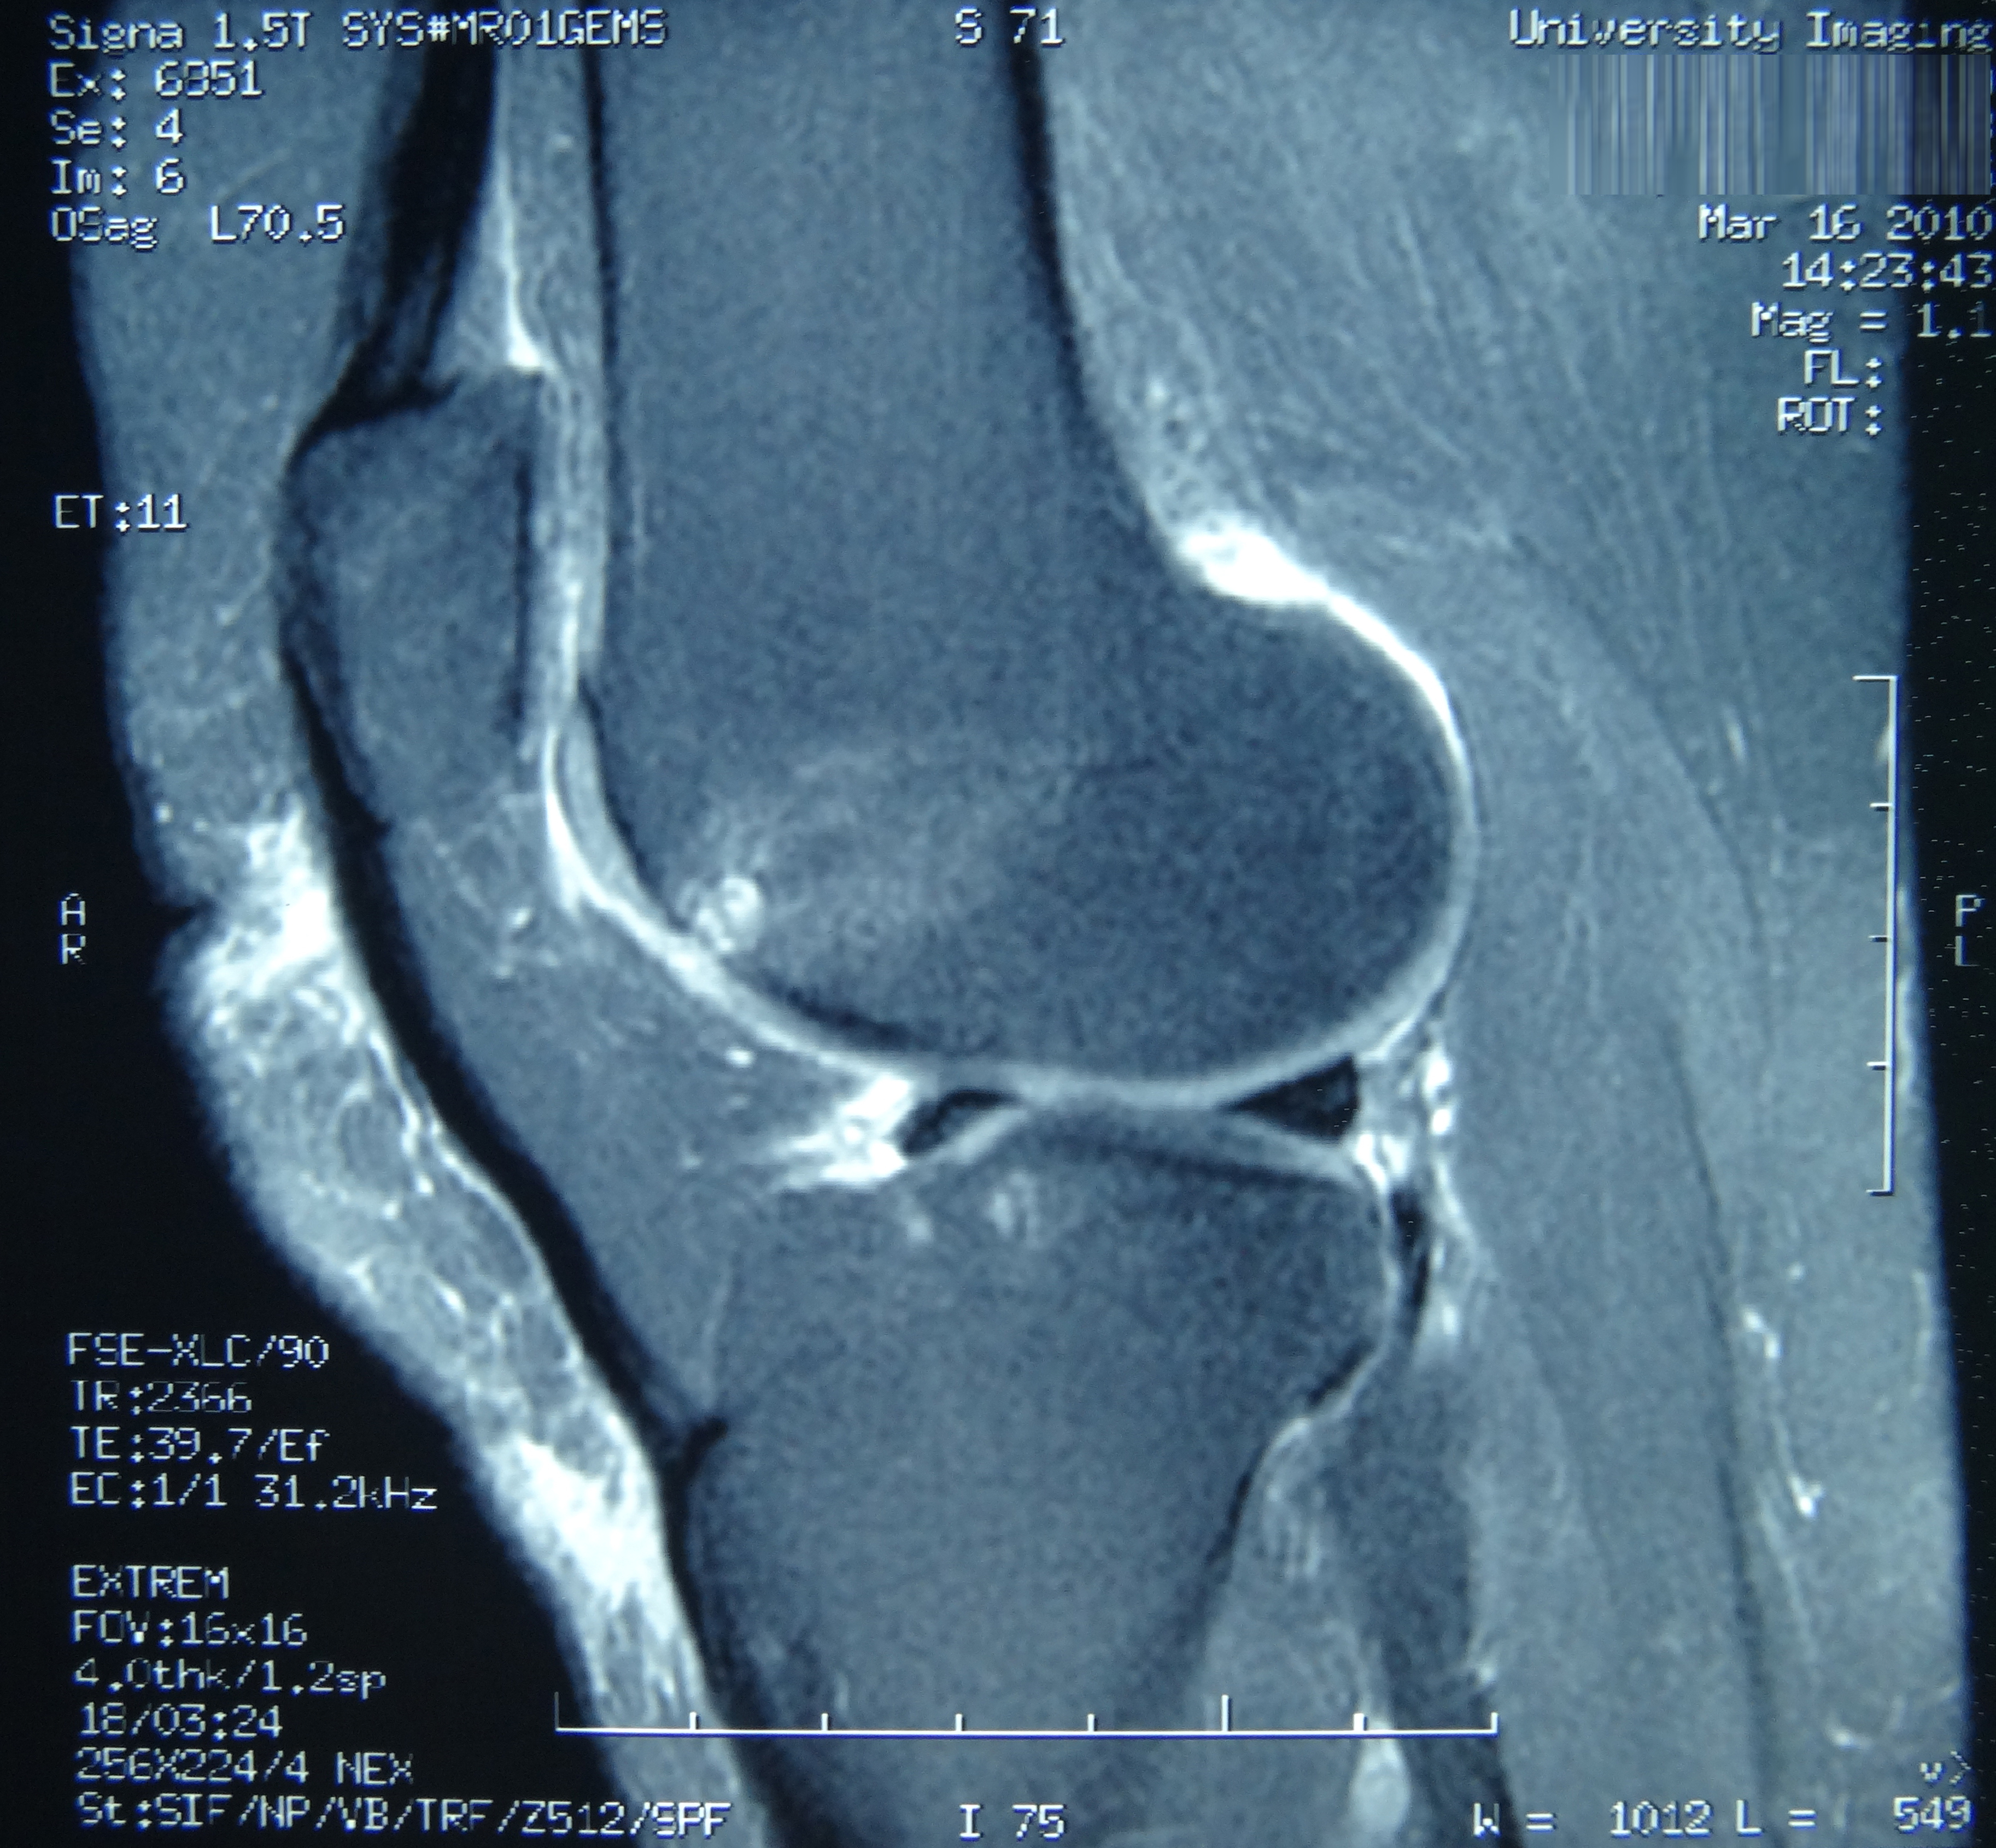

May 2019 MRI

IMPRESSION

- Near full-thickness tear of the anterior cruciate ligament femoral attachment with

associated edema in the intercondylar notch. This is best seen on axial and coronal

images. - Pivot shift bone contusions in a pattern typical of this injury.

- Medial meniscus: Complex tear of the posterior horn of the peripheral third

compromising superior and inferior articular surfaces, with the tear more horizontal

towards the posterior horn/body junction.